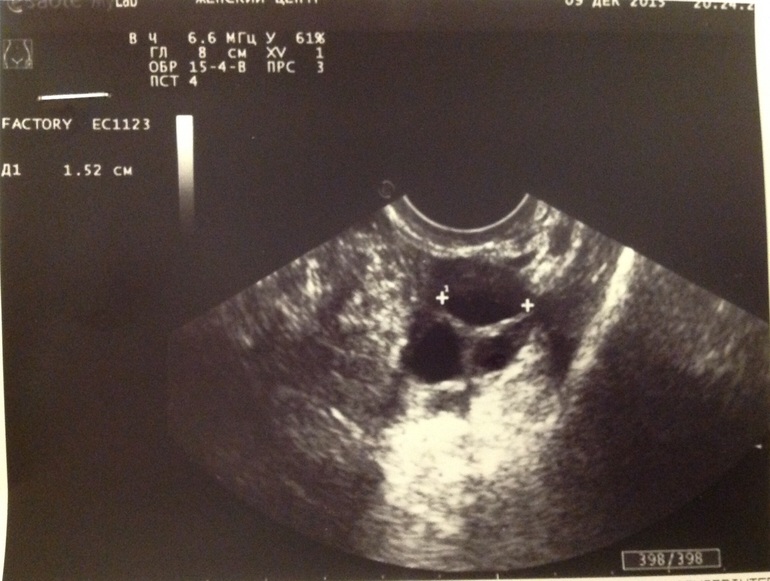

Результаты фолликулометрии. 17 ДЦ сегодня (цикл 31-35 дней).

ЛЯ фолик 13 мм

ПЯ фолик-1 15,2 мм, фолик-2 14,4 мм ИХ 2 выросло! Вот почему с правой стороны тянет оооочень сильно!

Эндометрий 7,5 (трехслойный).